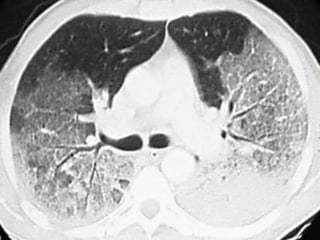

Diseased Lungs Do

Not Fully Collapse,

Despite Tension Pneumothorax

…and

They cannot always

be fully “opened”